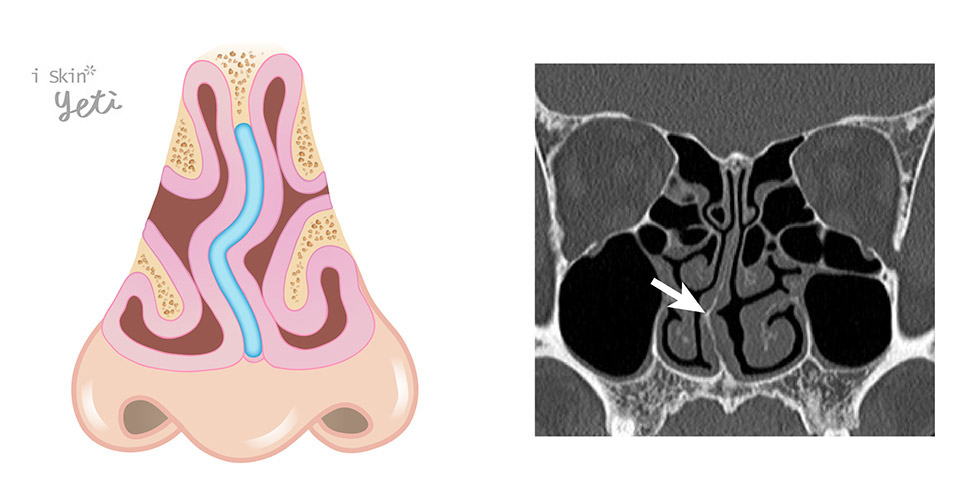

▲鼻腔分段示意圖。

▲鼻中隔彎曲常合併肥厚性鼻炎,造成鼻道空間狹小,影響氣流因而有鼻塞的現象產生。